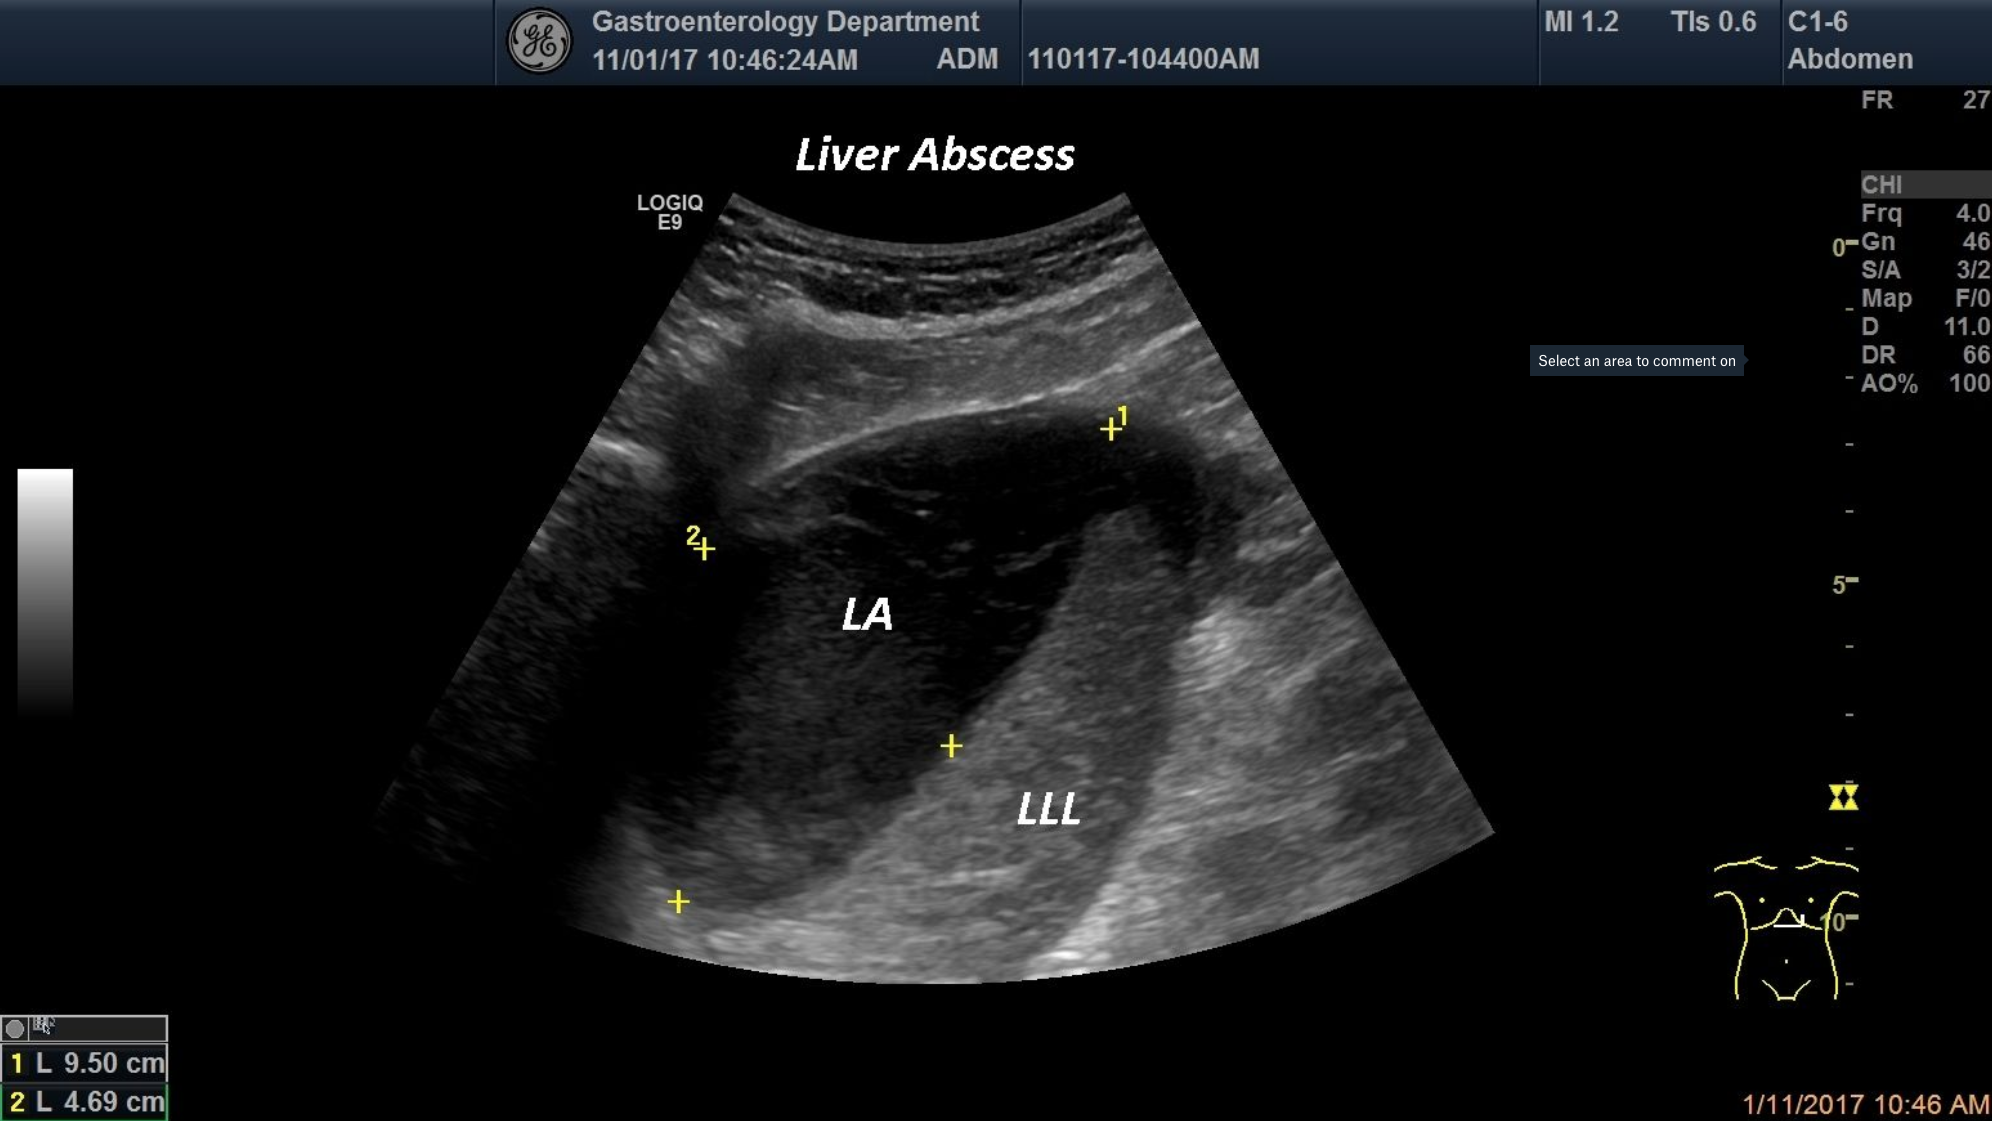

TITLE: Liver Abscess

A patient was admitted intothe Gastroenterology department for fever, fatigue and malaise. At standardultrasounda well delineated,heterogeneous-anechoic structure in the left liver lobewas depicted. Aspiration was performed and the content turned out to be pus, thus proving the diagnosis of liver abscess

focal liver lesion, liver abscess, anechoic structure